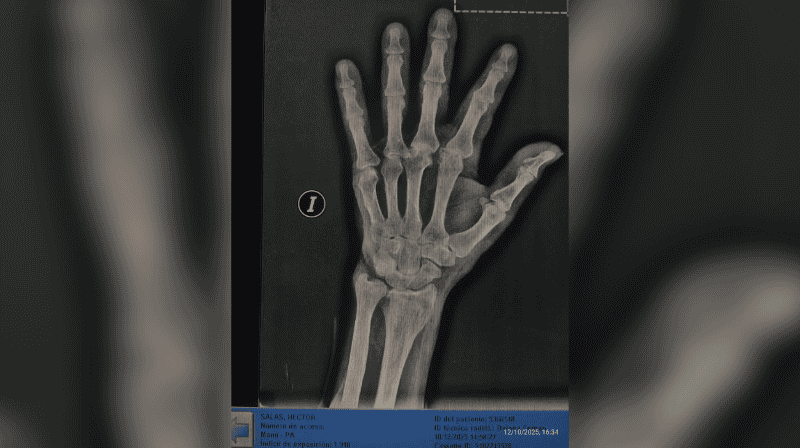

La nieta de la víctima, Karen Salas, realizó una denuncia pública a través de las redes sociales. “Él se negó a tomar una medicación y ella (la dueña del geriátrico) fue y le pegó. Según ella, dijo que le pegó porque le agarró un brote psicótico”, expresó. En su publicación, compartió imágenes del abuelo, registros de las cámaras internas del establecimiento y las radiografías realizadas después.

Luego de la agresión, Héctor fue retirado del geriátrico y trasladado a otro establecimiento. La familia indicó que, durante una revisión médica solicitada por sus nietas, se confirmaron fracturas en el dedo pulgar derecho y heridas en el rostro.